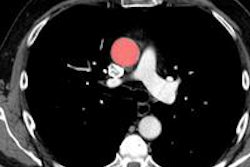

The core topics this year are inflammatory brain diseases and the imaging and treatment of tuberculosis. Alongside this, we shall discuss radiological research and offer an image quiz in musculoskeletal radiology, chest, and abdomen. We shall also talk about imaging and interventional treatment of echinococcosis, and the program features a session on "Blunt trauma to the torso." This final session already looks forward to this year's Turkish annual congress in Antalya, which this autumn will be followed directly, at that location, by the annual congress of the European Society of Emergency Radiology (ESER). This is definitely a sign that cooperation is being deliberately stepped up.